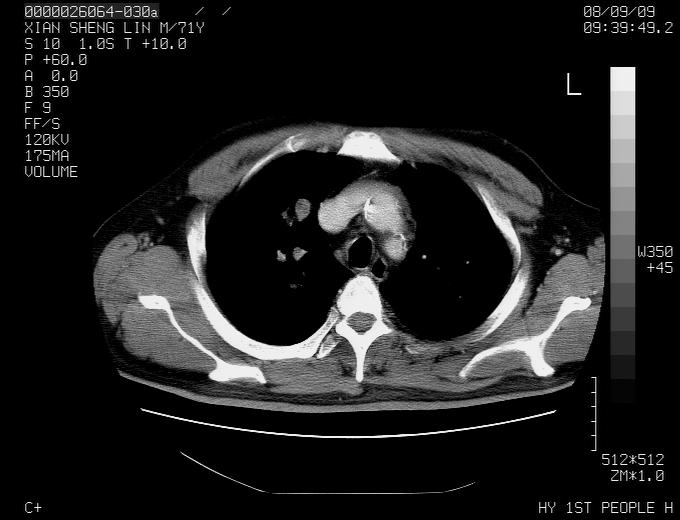

标题: CT15869:男性,71岁,因咳嗽而就诊,请讨论右上肺病变性质 [打印本页]

标题: CT15869:男性,71岁,因咳嗽而就诊,请讨论右上肺病变性质

患者,男性,71岁,因咳嗽而就诊,

典型的右肺中心性肺癌并纵隔淋巴结转移

右肺中心性肺癌并纵隔淋巴结转移可能性大!

病灶中等程度强化 还是支持肺癌诊断

考虑右肺中心性肺癌并右肺门及纵隔淋巴结转移。

1,右肺中心型ca,气管隆突旁淋巴结转移。

2,右膈明显抬高,建议肝脏扫描排除转移或原发灶。